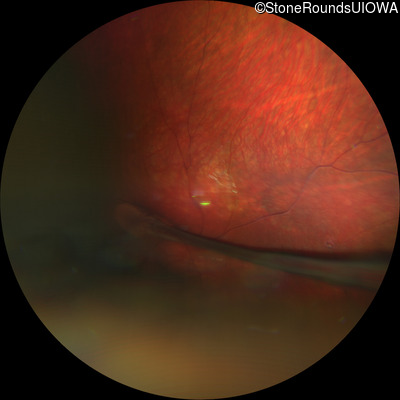

Fundus Photography - Left - 20/250

Exemplar